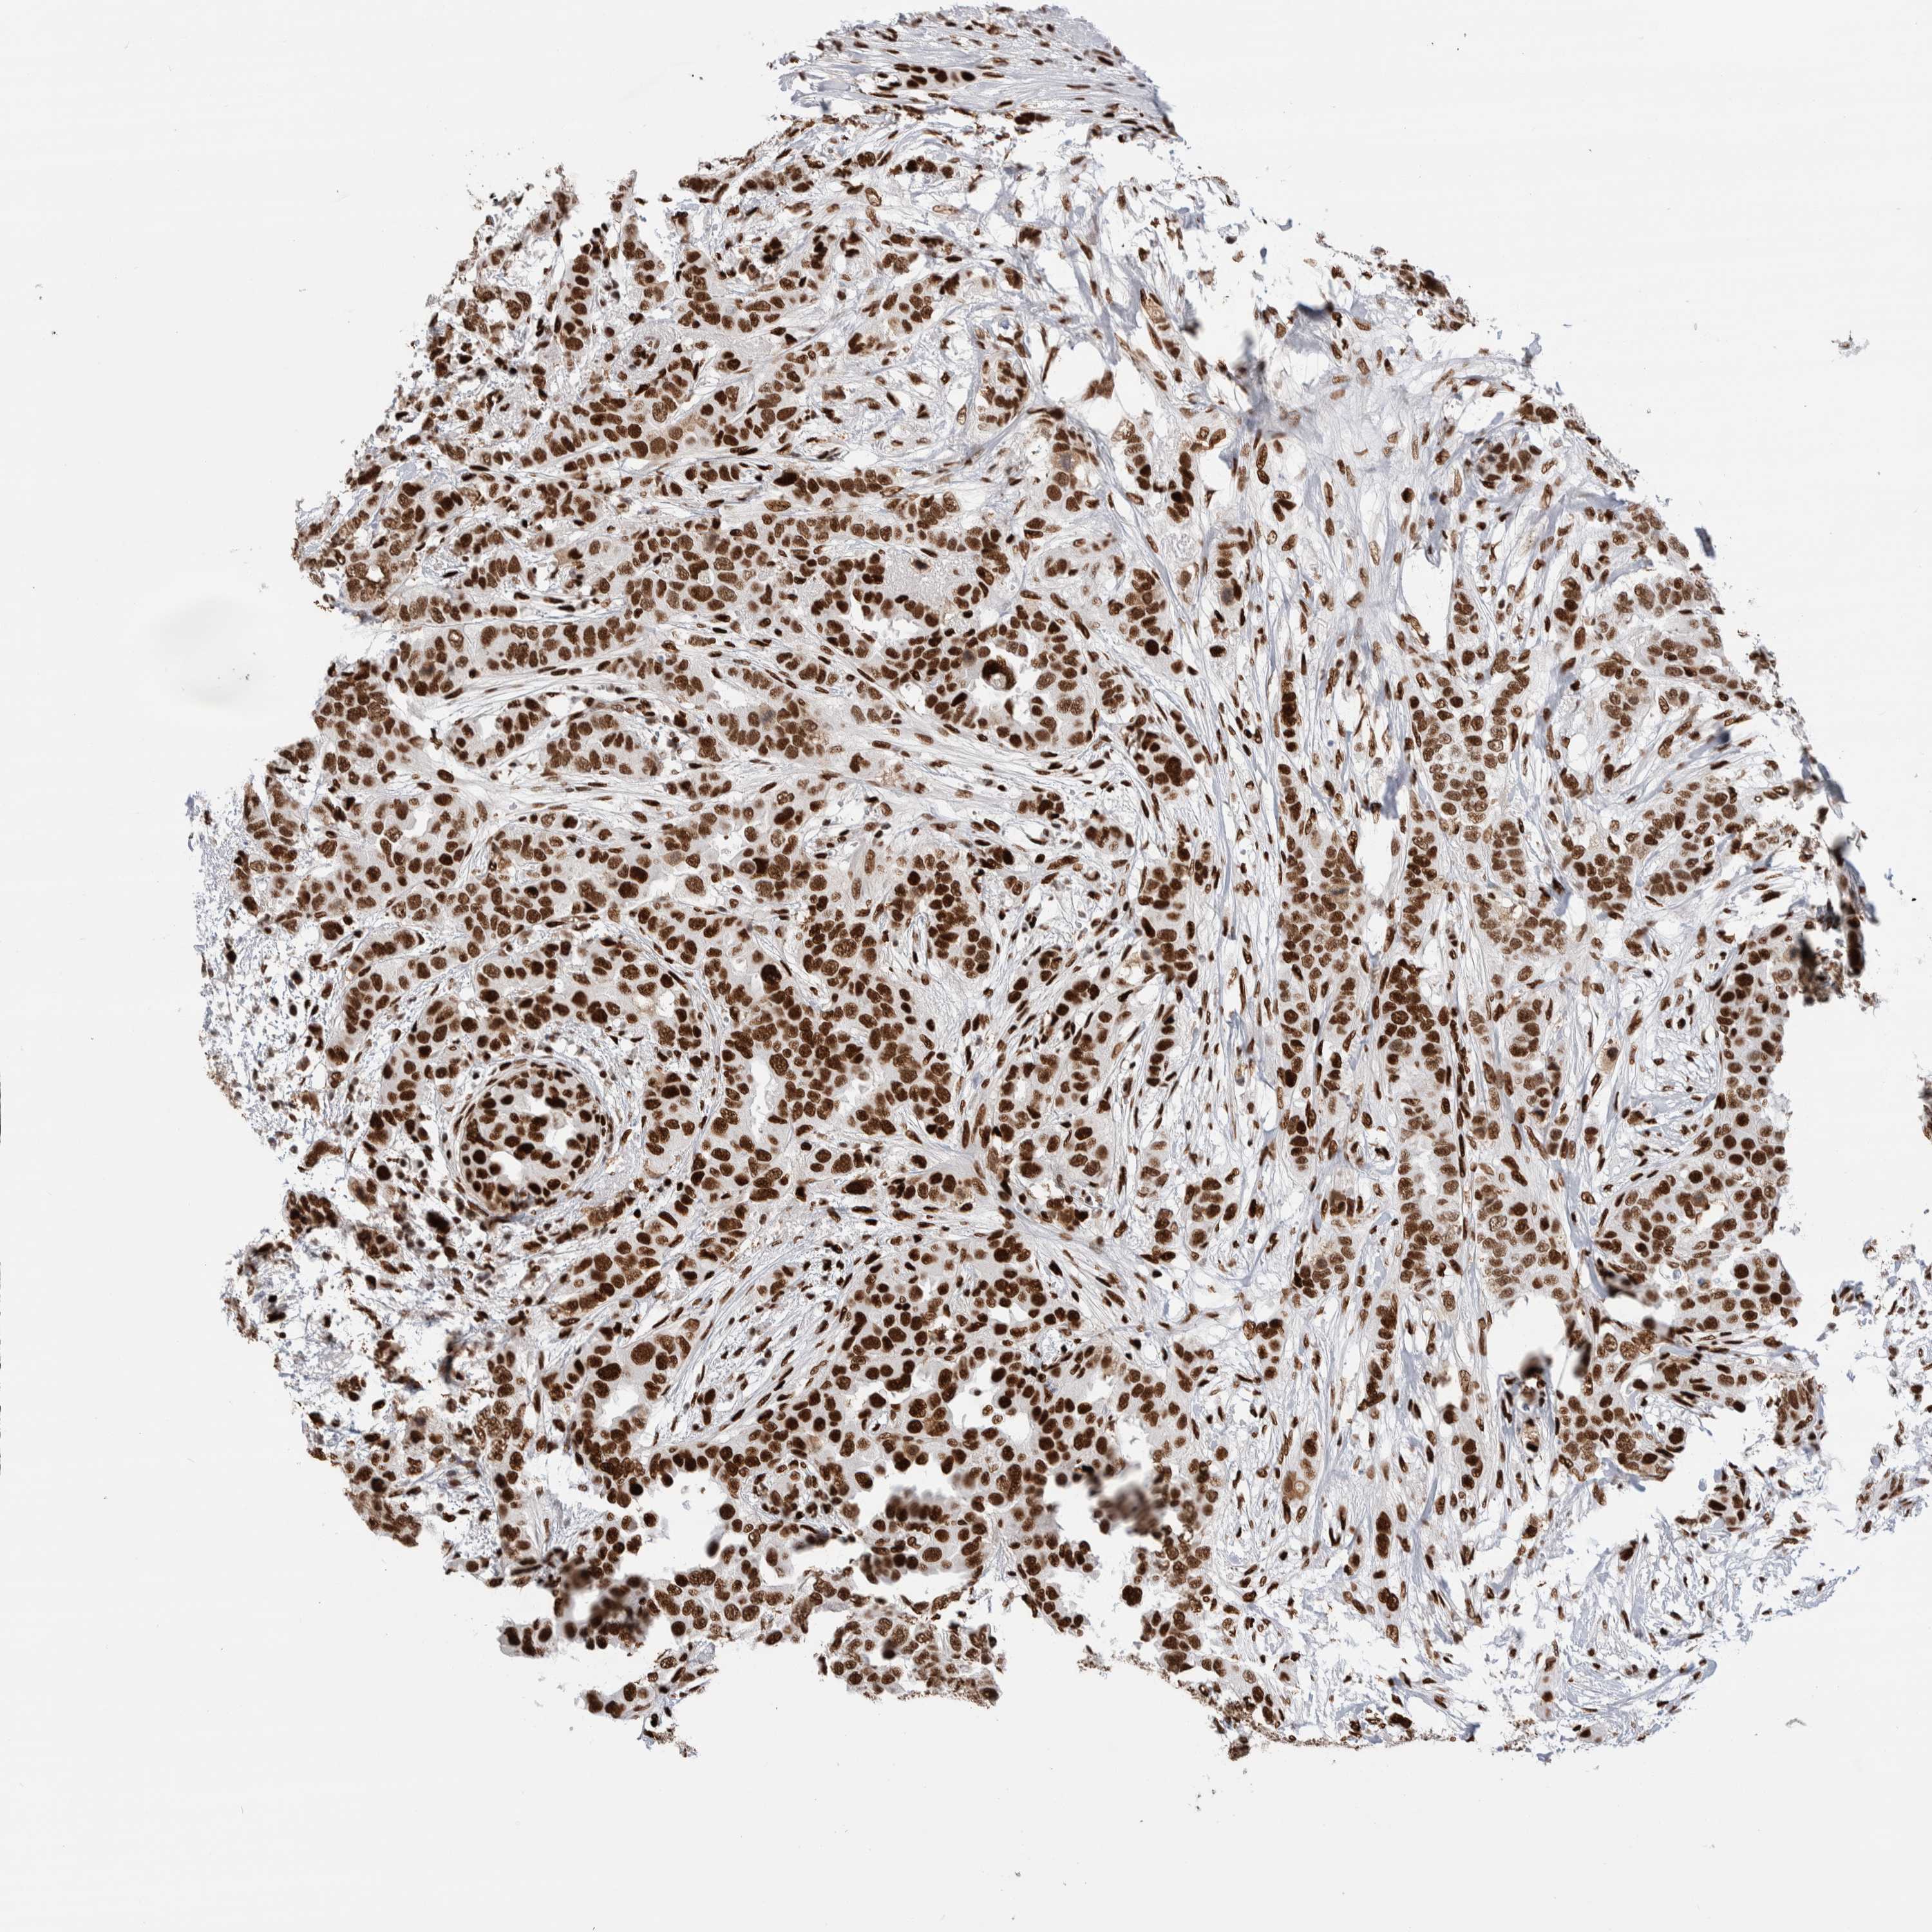

BRCA TCGA BRCA VALIDATION PROTEIN EXPRESSION